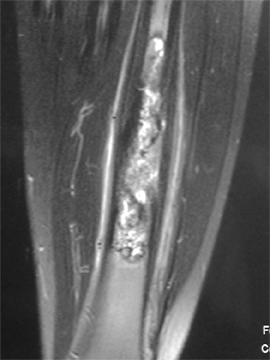

Malignes :

Ostéosarcome,

sarcome d’Ewing, autres cancers